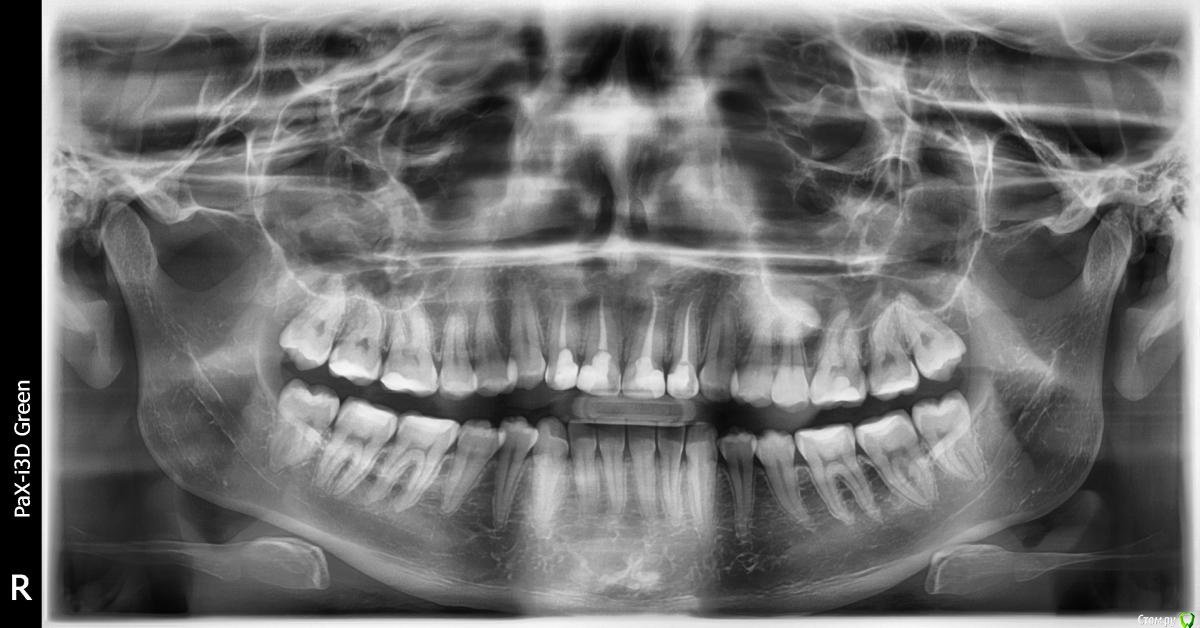

Puppy_Blue Опубликовано 27 марта, 2017 Поделиться Опубликовано 27 марта, 2017 Здравствуйте. Уважаемые врачи, помогите, пожалуйста, разобраться в том "кто прав, а кто виноват". Один врач-стоматолог говорит "есть штифты на передних зубах", другой - нет. Или может быть по этому снимку вообще невозможно увидеть их наличие или отсутствие? Ссылка на комментарий

shishok Опубликовано 27 марта, 2017 Поделиться Опубликовано 27 марта, 2017 Штифтов не вижу. 4 Ссылка на комментарий

Zlata-doctor Опубликовано 27 марта, 2017 Поделиться Опубликовано 27 марта, 2017 штифтов нет. А надо? 1 Ссылка на комментарий

AndyAndy Опубликовано 28 марта, 2017 Поделиться Опубликовано 28 марта, 2017 Я ортопед, выскажу своё мнение. Зубы восстановлены на 70% пломбами, тут однозначно коронки и однозначно культевые вкладки. Под установкой Сирона скорее всего предполагается кад/кам изготовление. Тут есть ньюанс по прозрачности этих коронок, а именно проницаемость для культевых вкладок. Вкладки лучше делать из драгметаллического сплава (если бюджет позволяет), они желтоватого цвета и будет норм. Обсудите с вашим доктором эти вопросы 1 1 Ссылка на комментарий